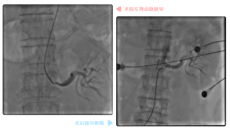

手术按级别分为四级,其中四级手术技术难度最大、手术过程最复杂、风险度最高。能否拿下四级手术,是评判一个手术团队实力的重要指标。 近日,广西国际壮医医院脾胃肝病科便碰上了一台四级手术,且该手术必须使用一种专科内最高端的内镜技术...... 腹痛、呕吐 竟是因为肚子里长了个“大瘤子” 谭女士今年66岁,10月下旬,她再次因腹痛、呕吐、没有食欲等症状前来广西国际壮医医院脾胃肝病科就诊。 5月上旬,谭女士曾因重症急...12.022021

胸闷,多数人觉得“缓一缓”就好了,岂不知这是一个危险信号,尤其对40岁以上人群来说,因为这些表现极有可能跟您的心脏有关。 近日,71岁的岑大爷因胸闷住进了广西国际壮医医院心病科。当时他的症状严重到“闷到只能躺床上,一下地就头晕、恶心、想吐”。 经检查,心病科主任徐先增很快找到了胸闷的“元凶”——冠状动脉粥样硬化性心脏病(以下简称“冠心病”)。 对于冠心病,医生通常会以介入手术疏通狭窄血管,使其恢复供血...12.022021